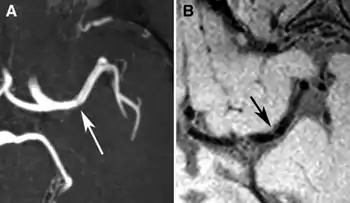

Partial anterior circulation infarct (PACI)[1] is a type of cerebral infarction affecting part of the anterior circulation supplying one side of the brain.